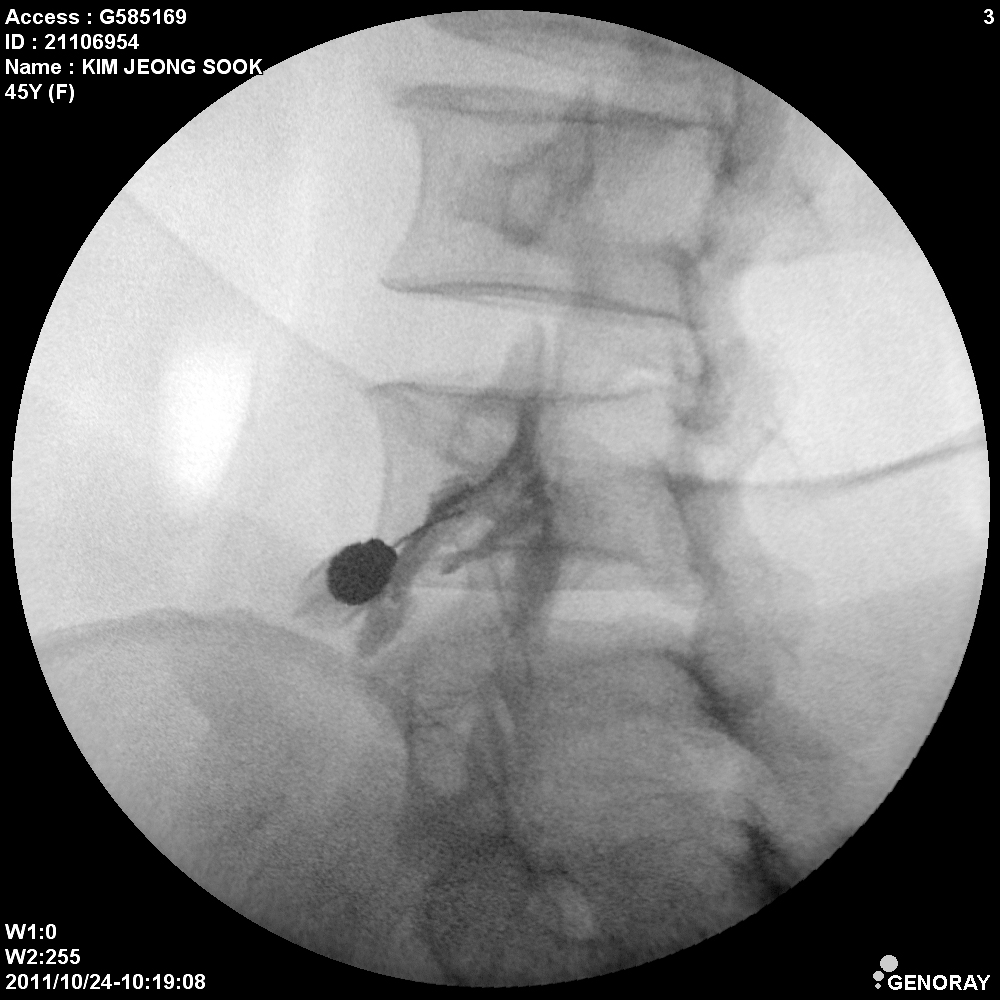

Аппарат применяется в различных областях медицины, таких как хирургия, ортопедия, педиатрия, травматология, урология и многих других. «РЕНЕКС-ОПТИМАЛ» имеет широкий диапазон перемещения и легко позиционируется во всех направлениях.

В качестве приемника используется усилитель рентгеновского изображения (УРИ) с ПЗС-матрицей 1024х1024 пикселей. Мощность рентгеновского питающего устройства 5,3 кВт. Система принудительного воздушного охлаждения, позволяет эффективно использовать аппарат на протяжении долгого времени без перегрева. Широкий диапазон регулирования количества импульсов при импульсной рентгеноскопии позволяет значительно снизить лучшею нагрузку, при этом при необходимости возможно проводить исследования с частотой до 30 кадров в секунду. С-дуга оснащена интерактивной сенсорной панелью управления всеми параметрами исследования на штативе аппарата.

- Непрерывная и импульсная рентгеноскопия с цифровой обработкой изображения.